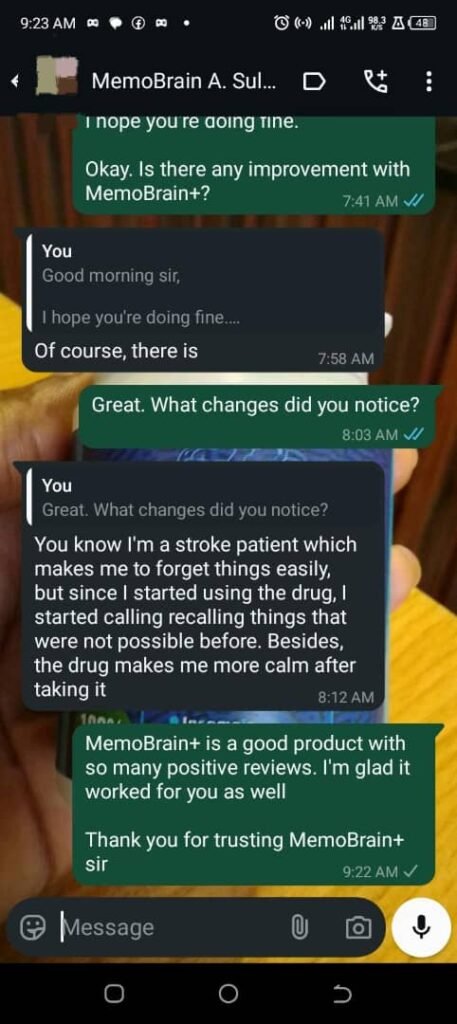

See what people are saying about MemoBrain+

Mrs Doris started remembering names she had forgotten in a long time… 3 days after taking this MemoBrain+

See the testimony below:

She’s not the only one

Don’t take my words for it…

See what people like you are saying about MemoBrain+

"The Product is a good one"

"There are lots of improvement"

See what real people like you are saying